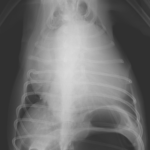

高齢(12歳)のアフガンハウンドが吐きたそうだけど、何も出てこない。次第に起立出来なくなったとのことで夜間に救急で来院しました。症状とエックス線検査から胃捻転と診断しました。また聴診時に心音は遠く、聴取出来ませんでした。胸部エックス線検査においてムーンハートが確認されました。超音波ガイドで出血性心のう水を2リットル抜去しました。バイタルサインが落ち着いたところで胃捻転整復術を実施しました。その後も出血性心のう水は貯留傾向にありました。高齢であることから血管肉腫が疑われましたが、各種画像診断においても腫瘤の存在はなくまた細胞診においても血管肉腫の可能性は低いものと判断しました。胃捻転から2週間後、心膜の生検と再発性の心膜貯留を回避する目的で心膜切除術を実施しました。心膜は顕著に肥厚し、線維化を伴っていました。病理検査の結果をもとに内科療法を併用する予定です。高齢ながら頑張ってくれました。